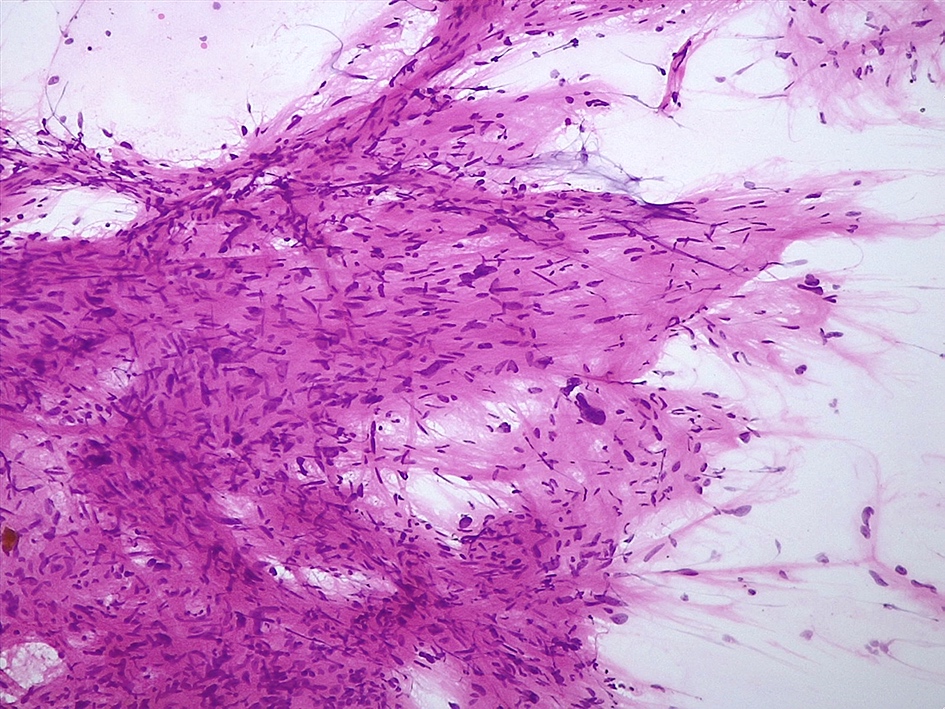

Intraoperative frozen / smear cytology images

Microscopic (histologic) description

- Spindle cell tumor (usually biphasic) and composed of compact hypercellular areas (Antoni A tissue) showing nuclear palisading (Verocay bodies) and loose microcystic areas (Antoni B tissue) with collection of lipid laden histiocytes and thick walled hyalinized blood vessels (Surg Neurol Int 2020;11:454)

- Lymphoid aggregates maybe seen peripherally or in a subcapsular distribution

- Mitoses or focal degenerative atypia may be present

- Ancient subtype: characterized by scattered atypical or bizarre nuclei

- Cellular subtype: composed exclusively or predominantly by Antoni A tissue and devoid of Verocay bodies

- Mitoses may be more conspicuous; uncommon in the CNS (Clin Neurol Neurosurg 2009;111:467)

- Epithelioid subtype: characterized by epithelioid cells with amphophilic or eosinophilic cytoplasm and uniform round nuclei with inconspicuous nucleoli

Microscopic (histologic) images

- Cohesive lesion with sharp borders in squash preparation or smear and composed of cells with spindle nuclei (Cytopathology 2022;33:196, Cancer Cytopathol 2015;123:171)

- Fibrillary matrix lacking cotton wool look at low magnification

- Hemosiderin deposition may be present (Cytopathology 2022;33:196)

- Nuclear hyperchromasia and pleomorphism may be present